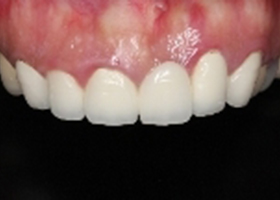

病患微笑時,假牙歪斜,牙齦不對稱。

proimages/case/cosmetic/pic_case-079.jpg

病患就診前口內照片。

右側假牙過短、左側正中門牙缺牙、左側側門牙牙齦萎縮,且牙冠過長。